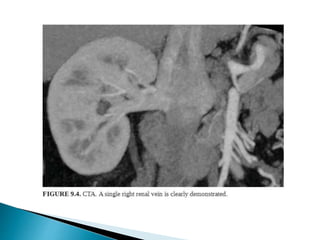

 CT is the preferred imaging due to better spatial resolution

and sensitivity to vascular calcifications and renal stones.

 CTA >> MRA

1. Distinguishing single/two main renal arteries.

2. Anatomy and to identify the point at which first branch

occurs.

3. Renal venous anatomy,

4. Tiny polar accessory arteries.

 Renal venous anatomy

◦ Retro-aortic/circum-aortic left renal vein.

◦ Duplicated right renal veins

◦ Distance between junction of vein with IVC and first

bifurcation

◦ Renal venous tributaries: adrenal/lumbar/gonadal

veins.